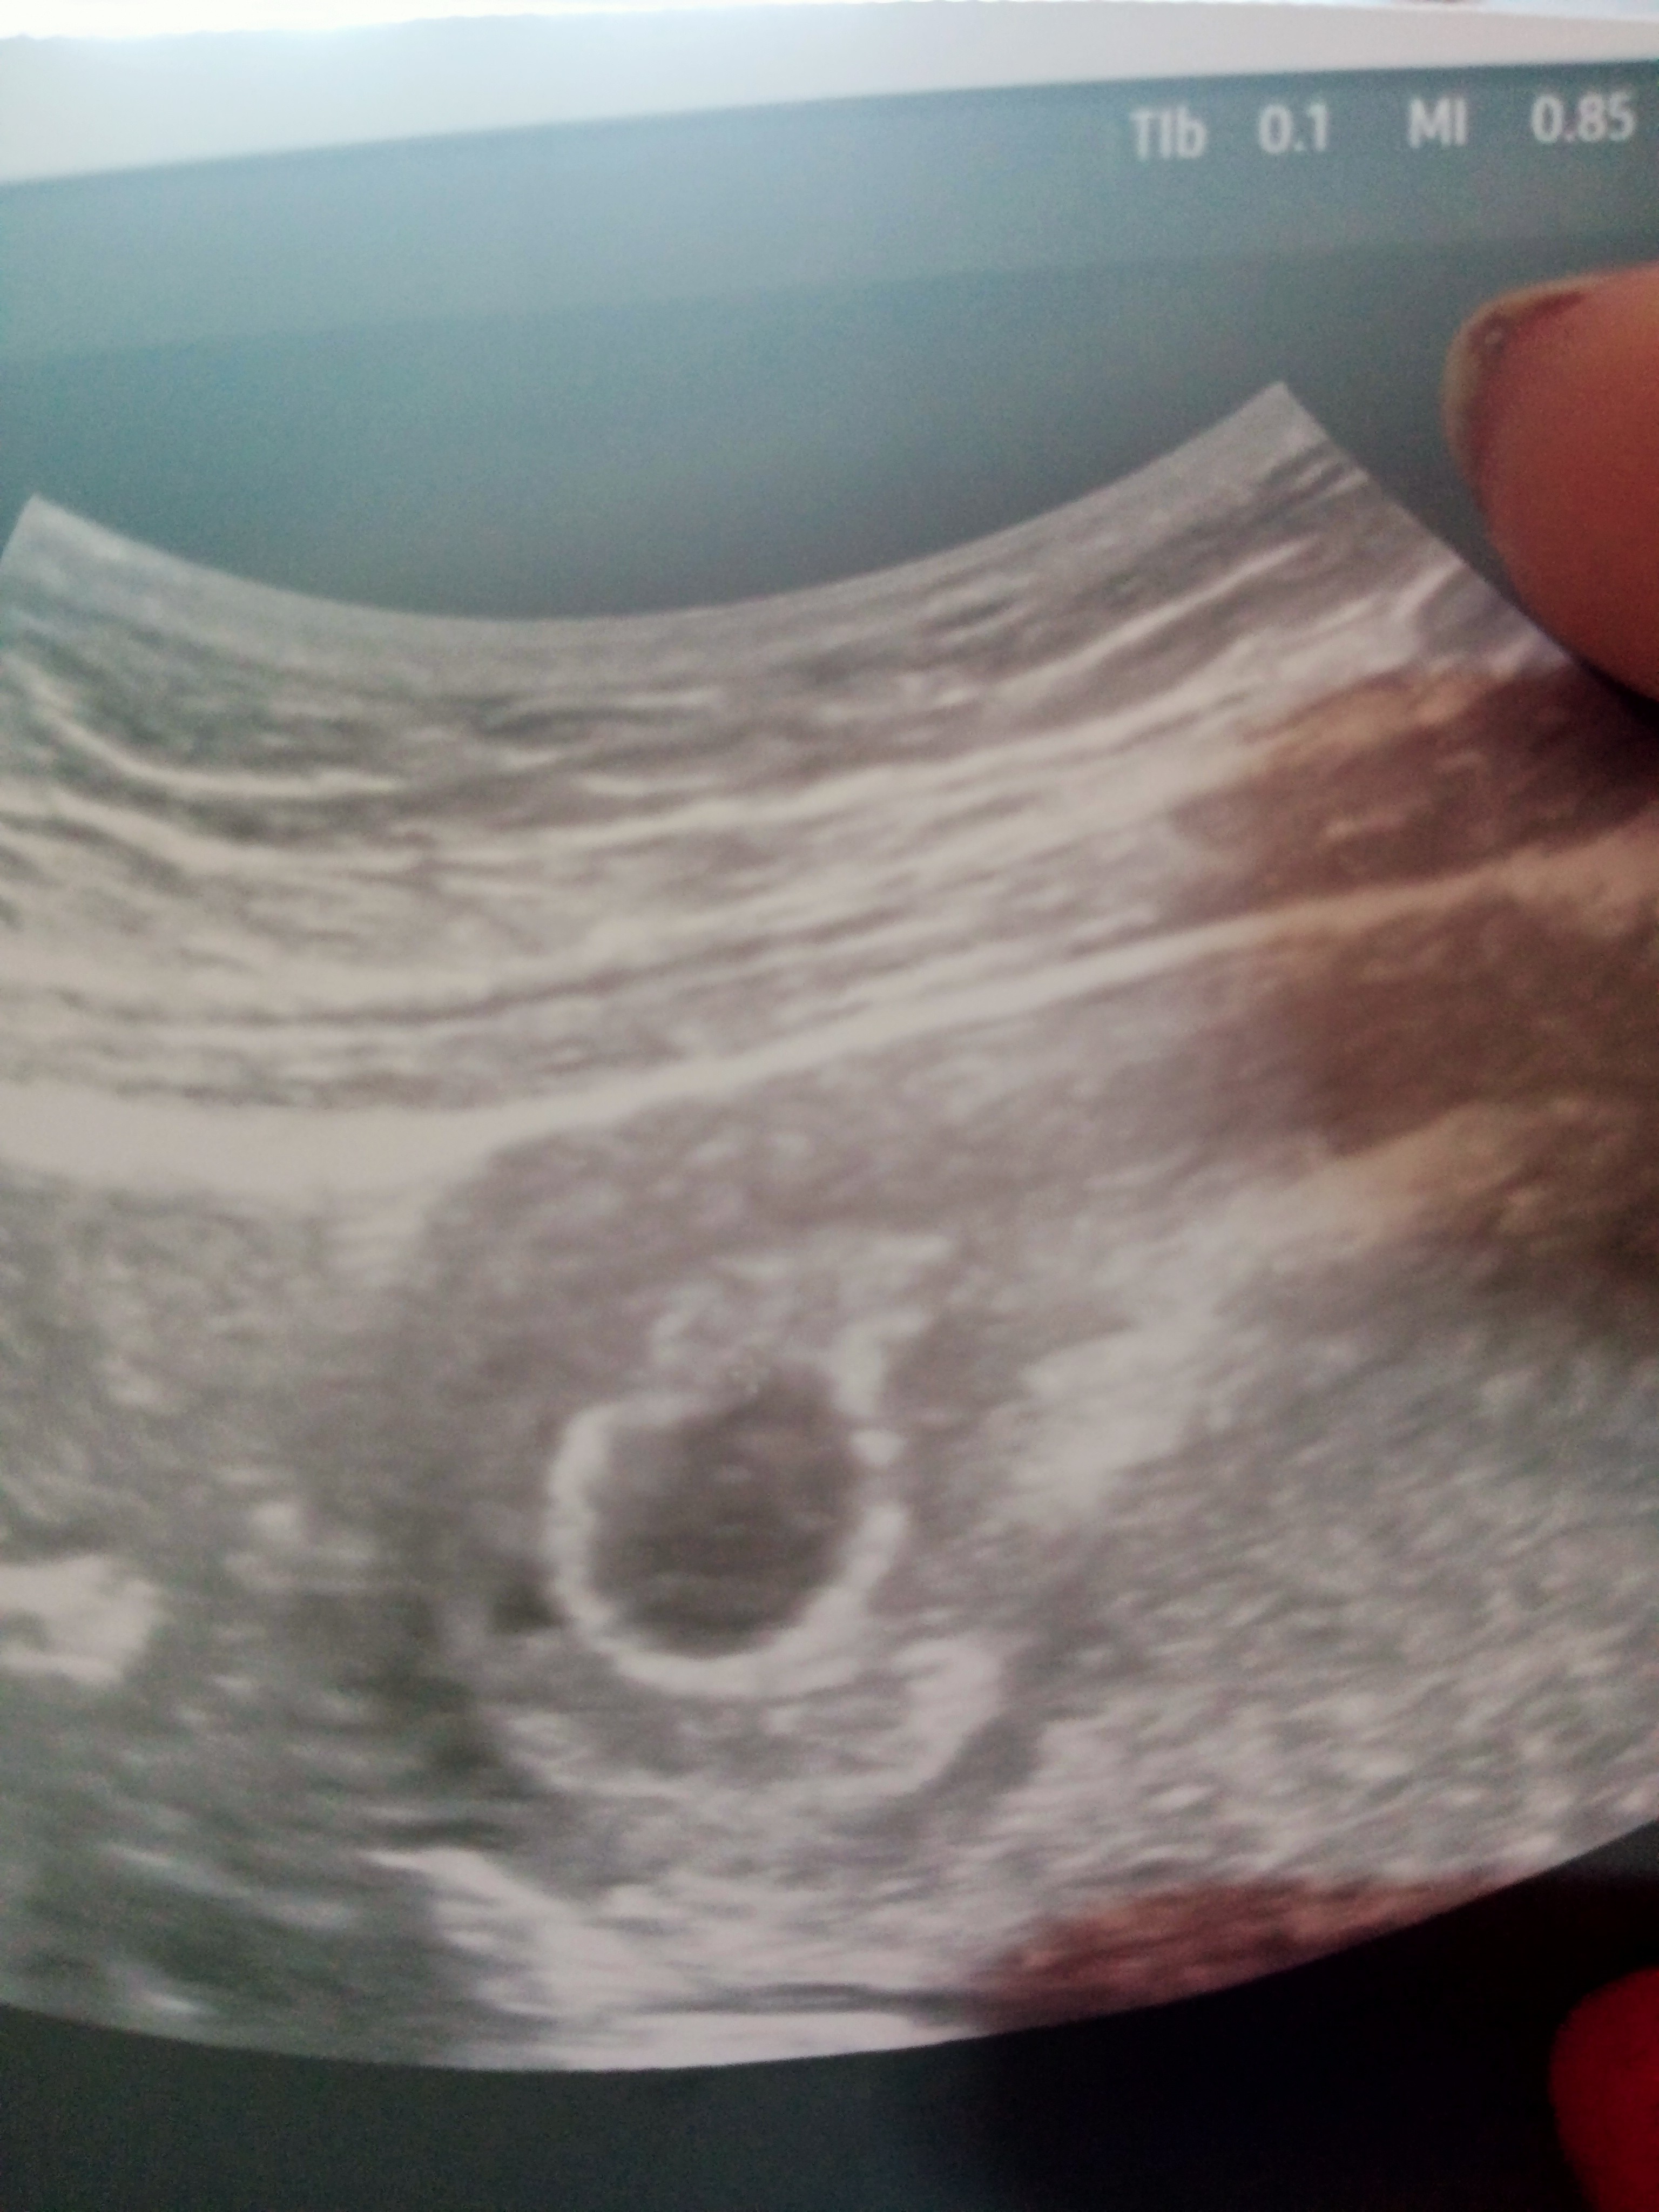

Ja mam usg prenatalne 3.06 i potem będę robiła amniopunkcje.

No właśnie. Hmm moze jednak ten kardiolog dziecięcy? Taki co sie specjalizuje w badaniu serca w płodu. Moja siostra u takiej dr byla wlasnie i ona jakby zrobiła jej 'prenatalne' wszystko jeszcze raz sprawdzila, serce dlugo i dokladnie badala i stwierdzila ze jest wszystko dobrze.Tak na usg wszystko ok. Tylko ta zasrana Pappa. No i pewnie jeszcze wiek, mam 35 lat i 2 poronienia.

ja właśnie się zastanawiam bo mam wizytę za półtora tygodnia a potem w 14 tyg już tez umówiona i teraz nie wiek które będą prenatalneDziewczyny, wszystkie będziecie robić badania prenatalne? Ja 02.06 mam następna wizytę, to będzie 12 tydzień, ale prenatalnych nie planuje...